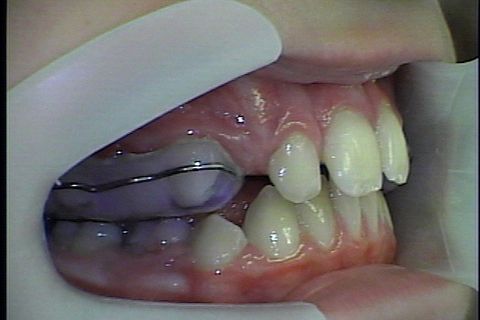

Uso do Twin Force por aproximadamente 3 meses

Twin Force

Paciente Classe II, já havia usado disjuntor por falta de espaço, durante tratameto foi usado o Twin Force para projeção da arcada inferior e melhora do encaixe em Classe I de canino,na finalização do caso vemos que a paciente possui Bolton Superior o que provavelmente gerará a necessidade de desgastes interproximais para concluirmos com uma finalização adequada do caso.